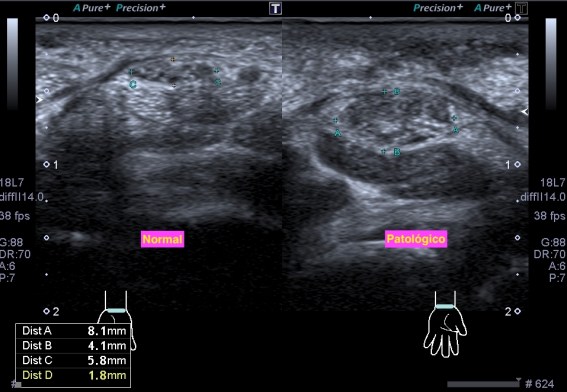

Un breve recuerdo anatómico de la zona tanto en eje largo como en eje corto (longitudinal o transverso), fig 3 y 2 respectivamente, . Fíjese la/el lectora en el posicionamiento del pictograma de referencia.

Acto seguido procedo a las mediciones en ambos planos:

Comprobando los cambios objetivados en la ecoarquitectura del músculo figuras 4 y 5, le pido al paciente que realice contracción del muslo normal y del patológico, observando claros cambios de la ecoarquitectura y de comportamiento en la exploración dinámica.Mira:

El Recto anterior afectado no se contrae correctamente (fig 6), de facto, casi no sufre variación respecto de su situación basal, el normal sufre una hipoecogenicidad aumentada, semiológicamente normal en la contracción (fig 7) y un cambio en su aspecto respecto de la situación de reposo muscular.